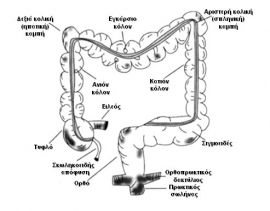

Κόλον Το παχύ έντερο αποτελεί τη συνέχεια του τελικού ειλεού, έχει μήκος 150 εκ και εκτείνεται από την ειλεοτυφλική βαλβίδα έως τον πρωκτό. Αποτελείται από το κόλον και το ορθό. Το κόλον αποτελεί ένα δομικά ενιαίο όργανο αλλά έχει διπλή εμβρυολογική προέλευση (Εικόνα 1). Το δεξιό κόλον (τυφλό, ανιόν και…

Ορισμοί Τα εκκολοπώματα είναι σακοειδείς προεκβολές του βλεννογόνου διά της μυϊκής στιβάδας του παχέος εντέρου. Αποτελούν βλεννογονικές κήλες που παρουσιάζονται στα «αδύναμα» σημεία εισόδου διατιτραινόντων αιμοφόρων αγγείων (μακρών κλάδων των ευθέων αγγείων) διά της μυϊκής στιβάδας. Τα σημεία εισόδου εντοπίζονται μεταξύ μεσεντέριας ταινίας και πλαγίων ταινιών (Εικόνα 1). Τύποι εκκολπωμάτων:…